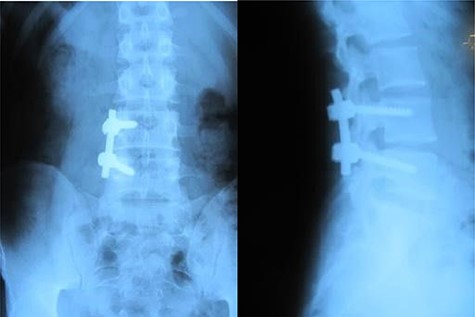

A 26-year-old male presented with pain over the lower lumbar area. Physical examination and laboratory tests were unremarkable with no neurologic deficit. X-ray and CT scans showed a lytic lesion with a sclerotic border in the right half of the body of the L5 vertebra (Figs 6 and 7). MRI showed a well-defined low signal lesion in T1 weighted images and high signal lesion in T2 weighted images (Fig. 8). The bone scan was negative. The patient underwent surgery and the lesion was extracted through the right pedicle and the remaining cavity was filled with an autologous bone graft from the iliac crest and right-side posterior fusion was done from L4 to L5 (Fig. 9). The pathology report was consistent with SBC. The patient had no recurrence seven years after surgery.